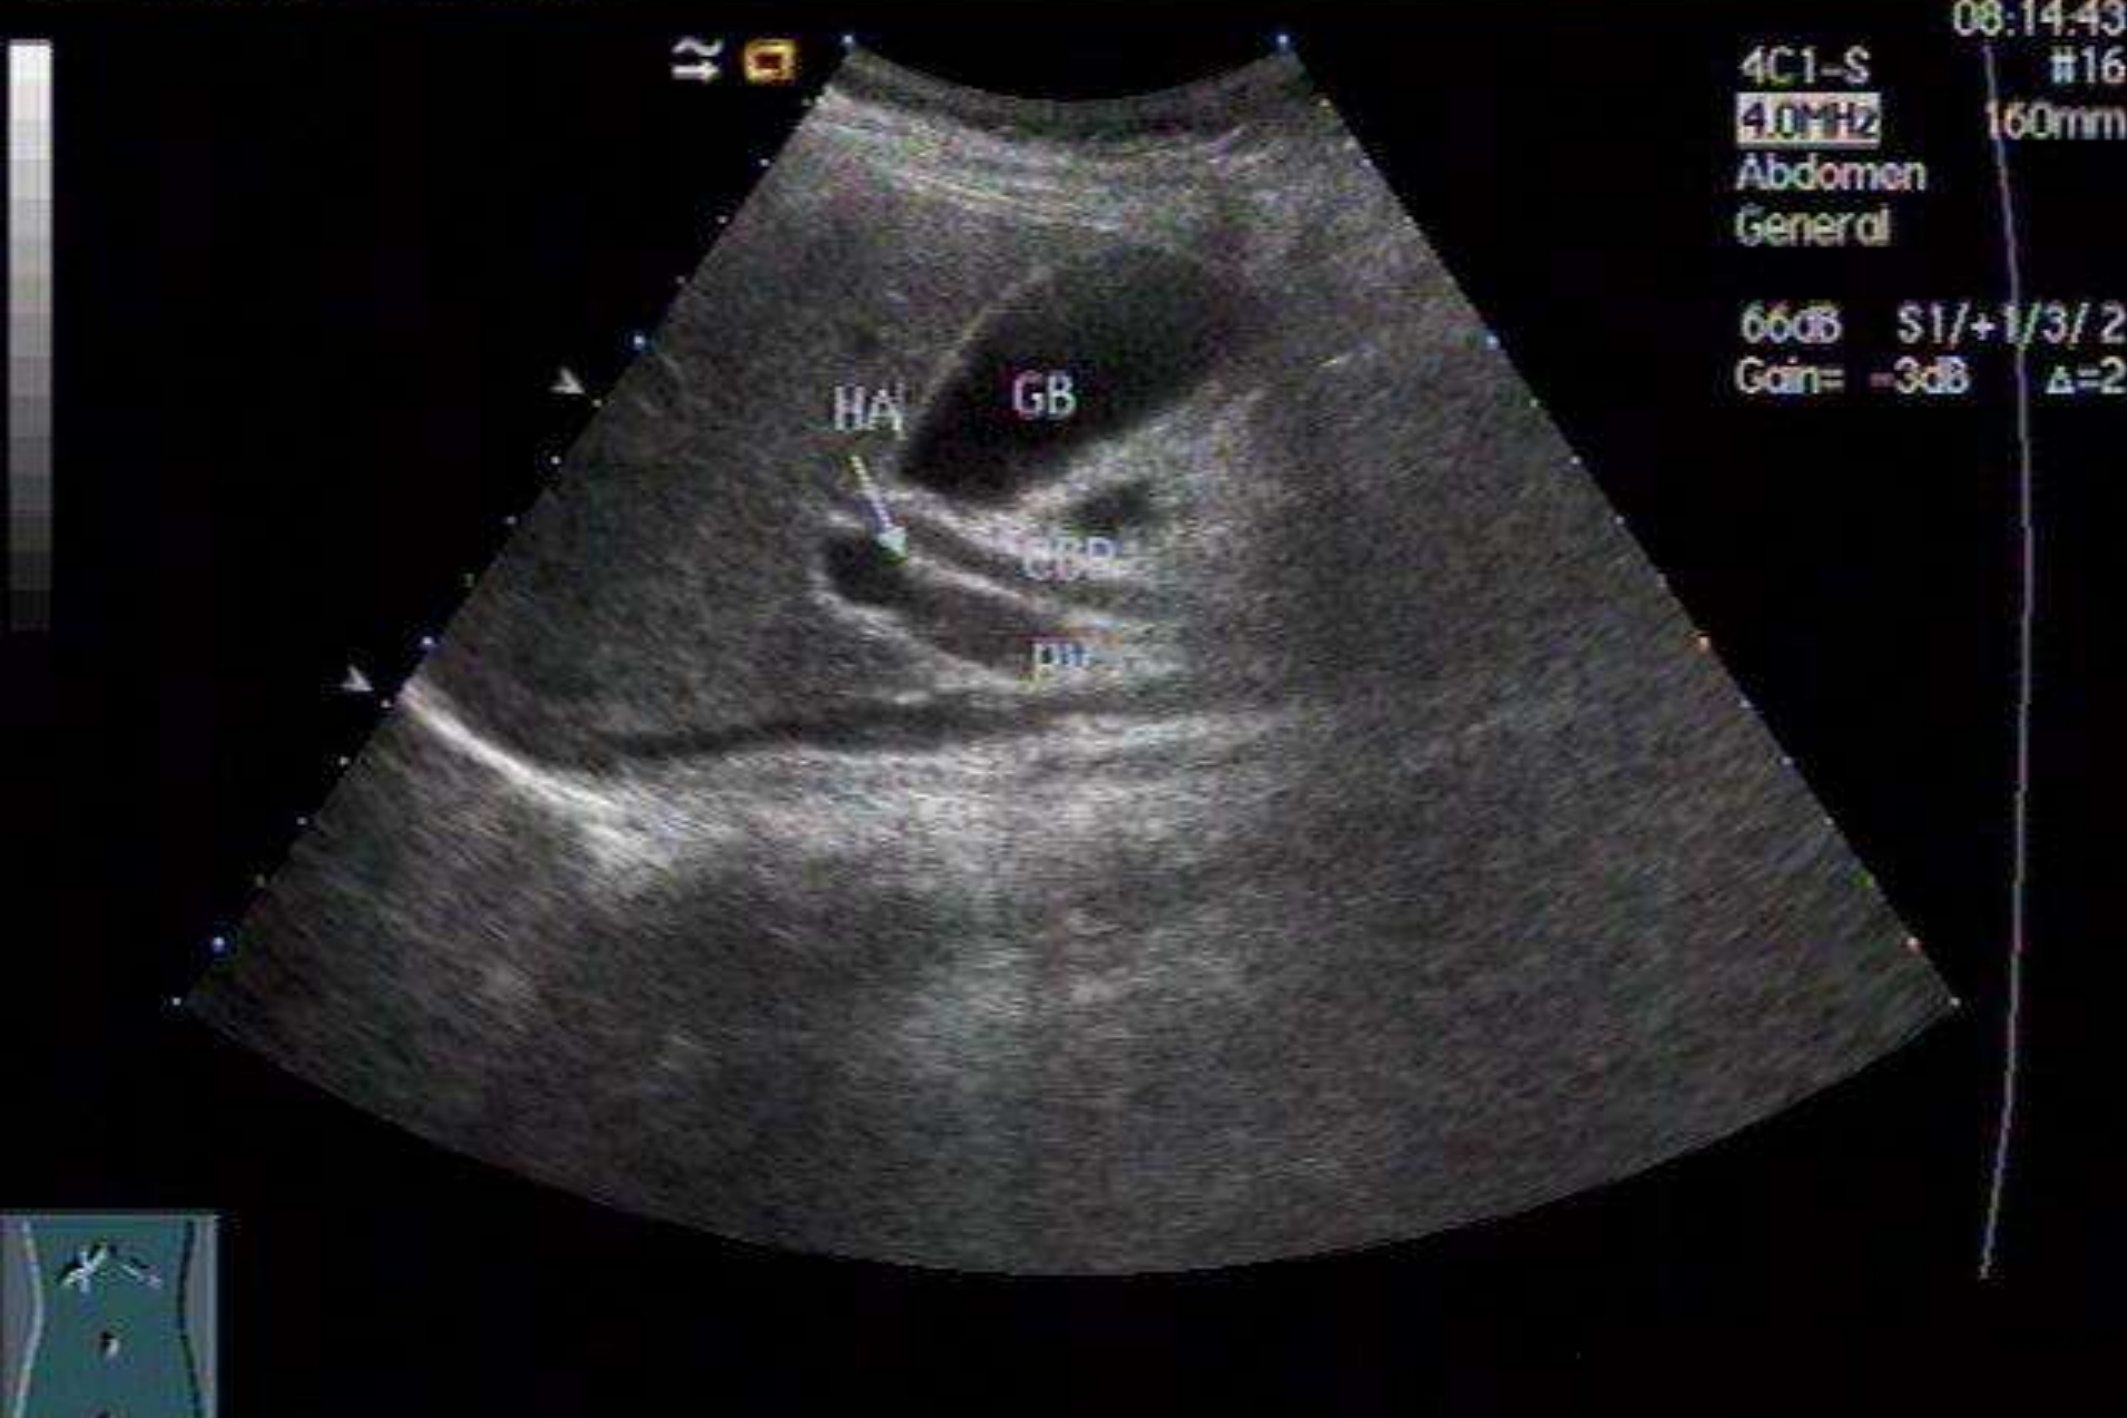

胆囊及胆管正常声像图

正常胆囊切面呈椭圆形或茄形,囊壁为轮廓清晰的光环,光滑自然,厚度不超过0.2cm。囊内为无回声区。超声测量长度不超过9cm,前后径不超过3cm。胆总管声像图分为上、下两段,上段位于门静脉前方,显示率达95%以上;下段因肠道气体回声干扰,显示率仅50%-75%。胆总管内径小于0.6-0.8cm。正常肝内胆管内径多为并行门静脉内径的1/3左右,一般不易显示。